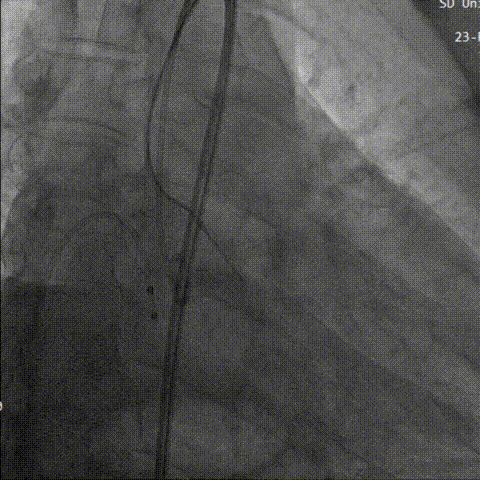

造影评估下瓣环上2mm定位,缓慢释放,瓣膜下滑到瓣环平面水平,瓣膜位置良好,继续释放到工作位进行评估,反流较为显著。决定再次回收。

回收后第三次进行瓣上2mm定位,确定释放位置稳定后没缓慢是放到工作位,猪尾导管造影显示无反流。

第三次定位

工作位评估

最后三分之一瓣膜稳定脱钩,造影显示,无明显瓣周漏及反流,瓣膜形态佳,工作稳定。

瓣膜完全释放

猪尾造影评估